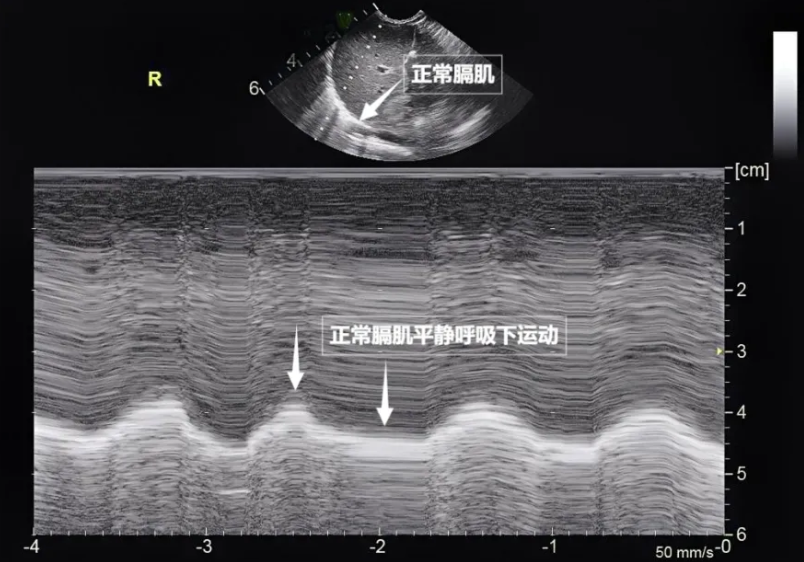

第三景:“呼吸的动力泵”的协同作战——呼吸肌肉呼吸看似简单,实则是多组肌肉精密配合的“团体操”。肺部超声不仅能观察肺的形态,更能通过实时动态影像,“捕捉”这些呼吸肌的活动状态,为评估呼吸功能提供独特视角。膈肌是呼吸肌的“总指挥”,位于胸腔与腹腔之间。平静呼吸时,膈肌收缩下沉,胸腔容积扩大,空气自然吸入;舒张时,膈肌回升,肺部弹性回缩完成呼气。超声下可见膈肌呈光滑弧形,随呼吸规律上下移动(见下图)。肋间外肌则是“肋间隙的升降机”,收缩时上提肋骨,扩大胸腔前后径,辅助吸气。这对“黄金搭档”承担了日常呼吸70%以上的工作量,是维持呼吸的“主力军”。

图为正常膈肌超声表现